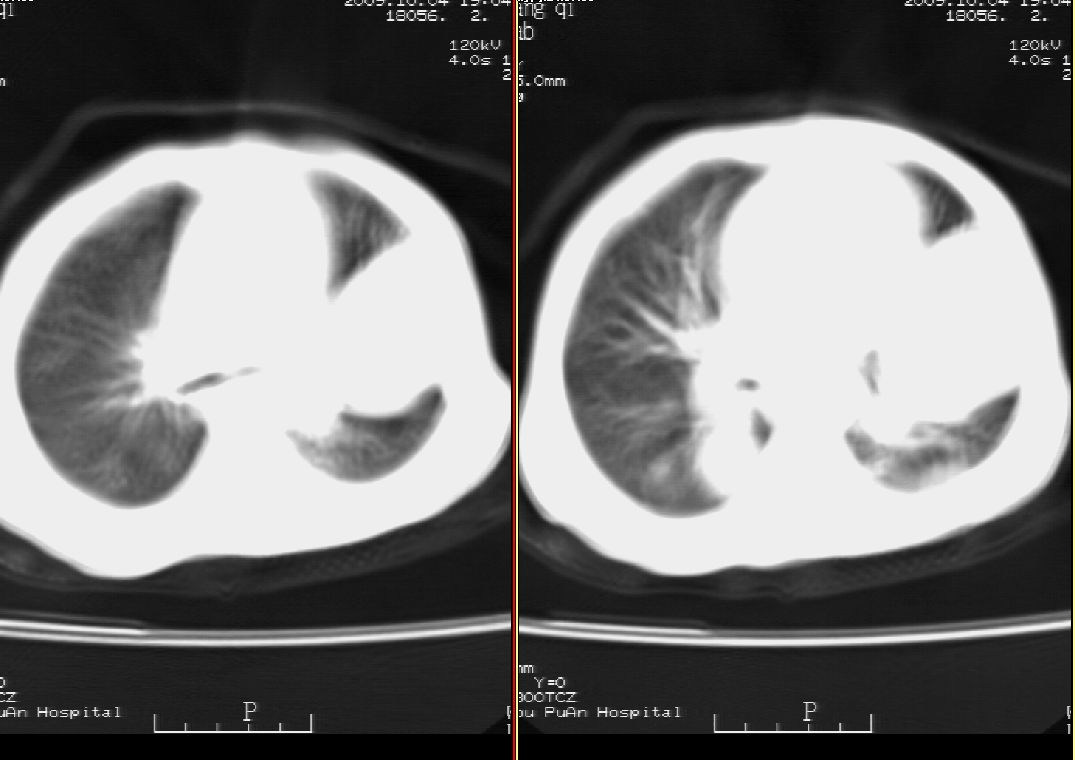

标题: PED2927:马某,男,两岁,发现血尿4天,请大家看看,发表 [打印本页]

标题: PED2927:马某,男,两岁,发现血尿4天,请大家看看,发表

右肾巨大囊性占位病变,其内密度不均,正常肾结构消失,肝脏,肾上腺及肠管等受压移位。双肺内多发大小不等的结节及块状影。考虑右肾母细胞瘤伴双肺多发转移。

ct表现:密度不均匀的大肿块存在;出血和坏死。与神母鉴别点:wilms易向颅脑转移,而神母易往肺转移。

ct表现:密度不均匀的大肿块存在;出血和坏死。与神母鉴别点:wilms易向肺转移。而神母易往颅脑转移.